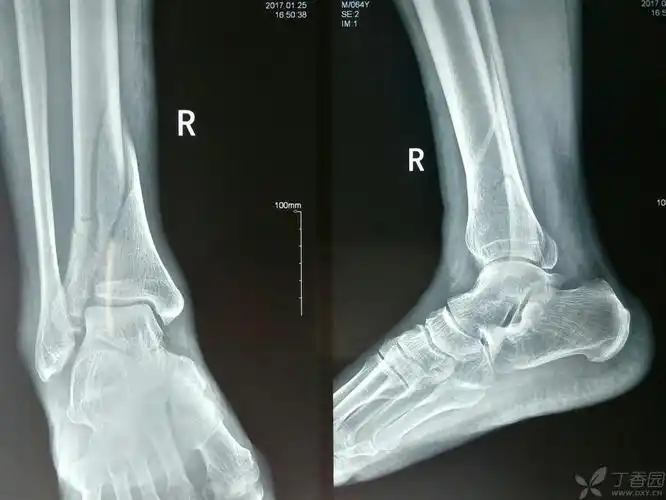

腓骨远端骨折